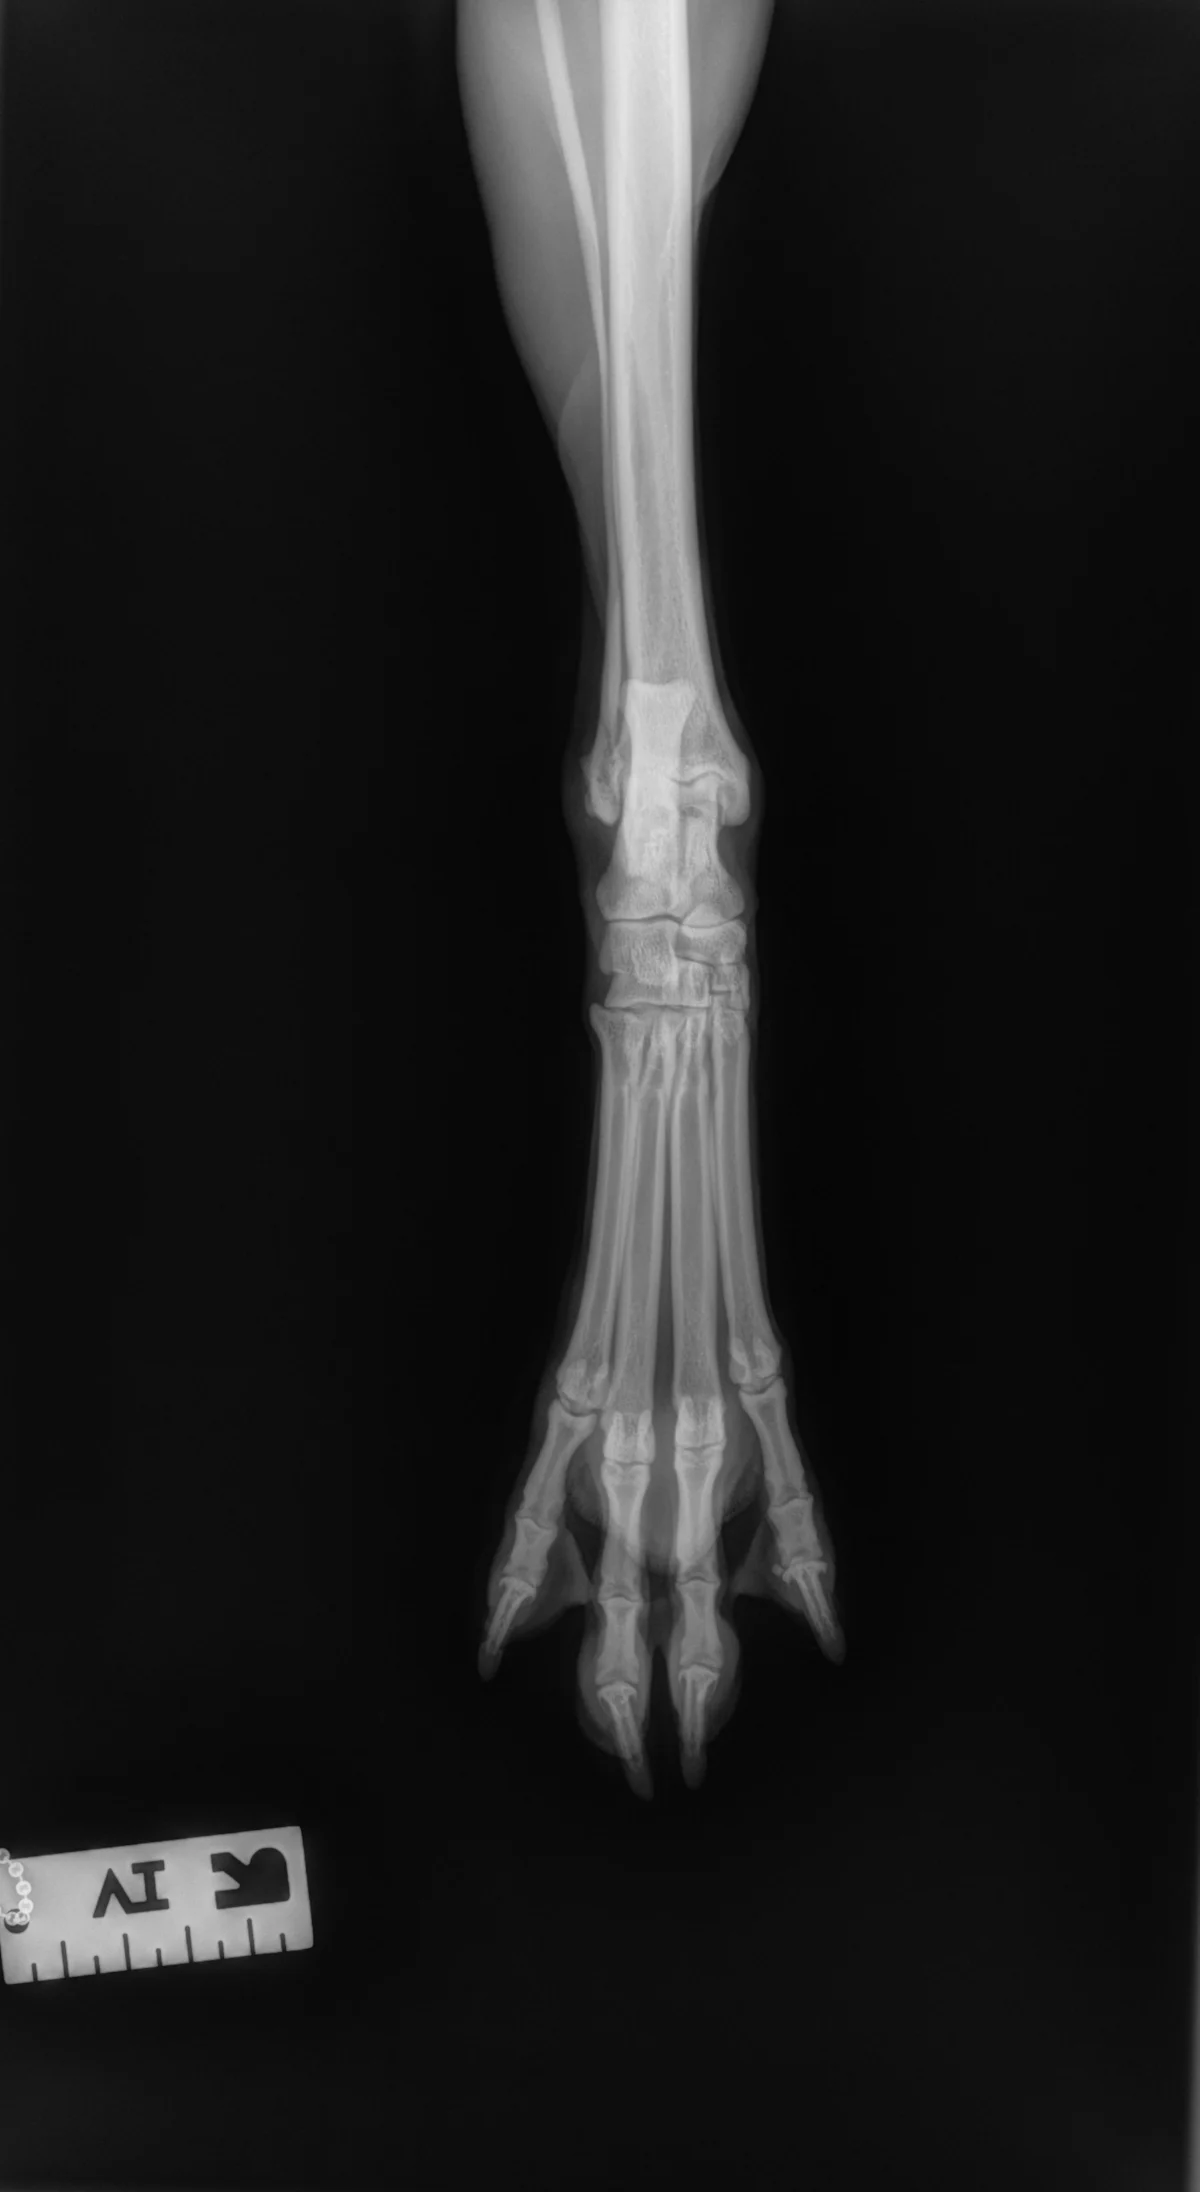

Author Insight

All digits should be separated and clearly visible. The bony edges of the metacarpal bones should be parallel to each other (arrows), and all phalanges (P1 [A], P2 [B], P3 and nail [C]) should be included.